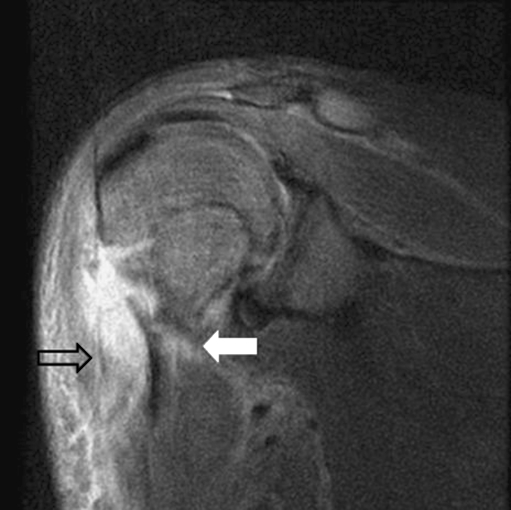

Despite anticoagulation and antibiotic administration, the patient’s clinical status failed to improve. On hospital day 5, MRI of the left upper extremity showed a focal area of cortical destruction on the lateral aspect of the proximal humerus with a 2.6×0.8×3-cm fluid collection on the anterior aspect (Fig. 2). The patient underwent operative exploration during which a subperiosteal soft tissue abscess was discovered anterior to the humeral metaphysis. Cultures subsequently grew MSSA. After intravenous antibiotic administration and extensive physical therapy, he was discharged from the hospital in stable condition.

Fig. 2.

MRI of the left upper extremity demonstrating focal cortical destruction on the lateral aspect of the proximal humerus (white arrow) and a 2.6×0.8×3-cm fluid collection anteriorly (black arrow); 279×123 mm (96×96 DPI)